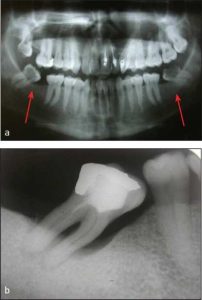

Following diagnostic cast surveying and treatment planning, tooth extractions should be carried out early enough to allow adequate healing. However, each tooth should be evaluated based on its location and potential contribution to the success of the treatment. Teeth that are strategically important and that will support the success of the prosthesis should be retained, while those with a questionable prognosis or that may complicate treatment planning should be extracted (Figure 10-1).